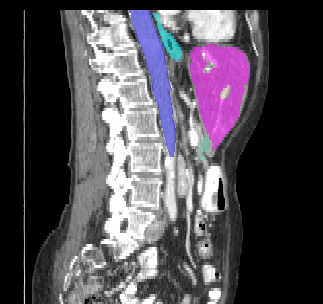

Recently, deep learning methods have achieved state-of-the-art performance in many medical image segmentation tasks. Many of these are based on convolutional neural networks (CNNs). For such methods, the encoder is the key part for global and local information extraction from input images; the extracted features are then passed to the decoder for predicting the segmentations. In contrast, several recent works show a superior performance with the use of transformers, which can better model long-range spatial dependencies and capture low-level details. However, transformer as sole encoder underperforms for some tasks where it cannot efficiently replace the convolution based encoder. In this paper, we propose a model with double encoders for 3D biomedical image segmentation. Our model is a U-shaped CNN augmented with an independent transformer encoder. We fuse the information from the convolutional encoder and the transformer, and pass it to the decoder to obtain the results. We evaluate our methods on three public datasets from three different challenges: BTCV, MoDA and Decathlon. Compared to the state-of-the-art models with and without transformers on each task, our proposed method obtains higher Dice scores across the board.